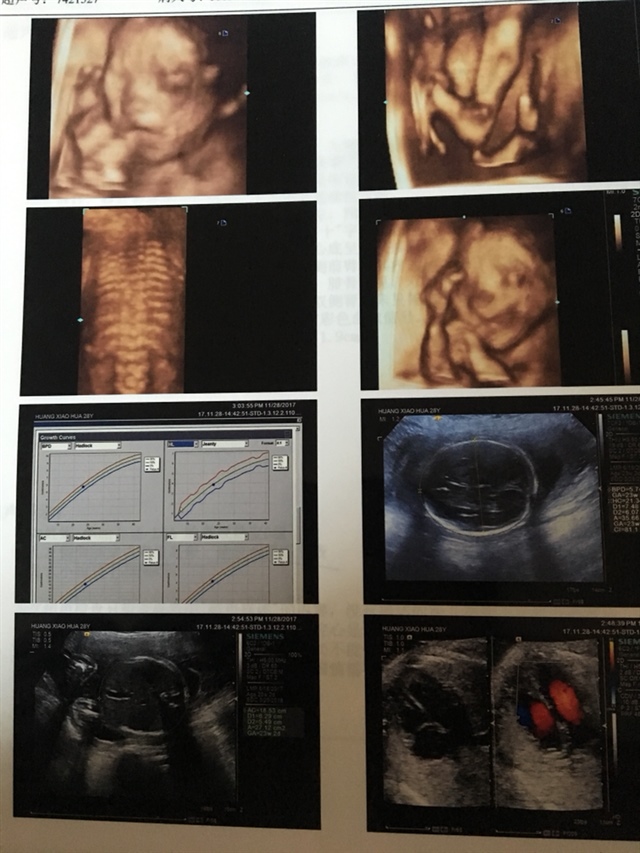

男宝,好像看见宝宝笑了